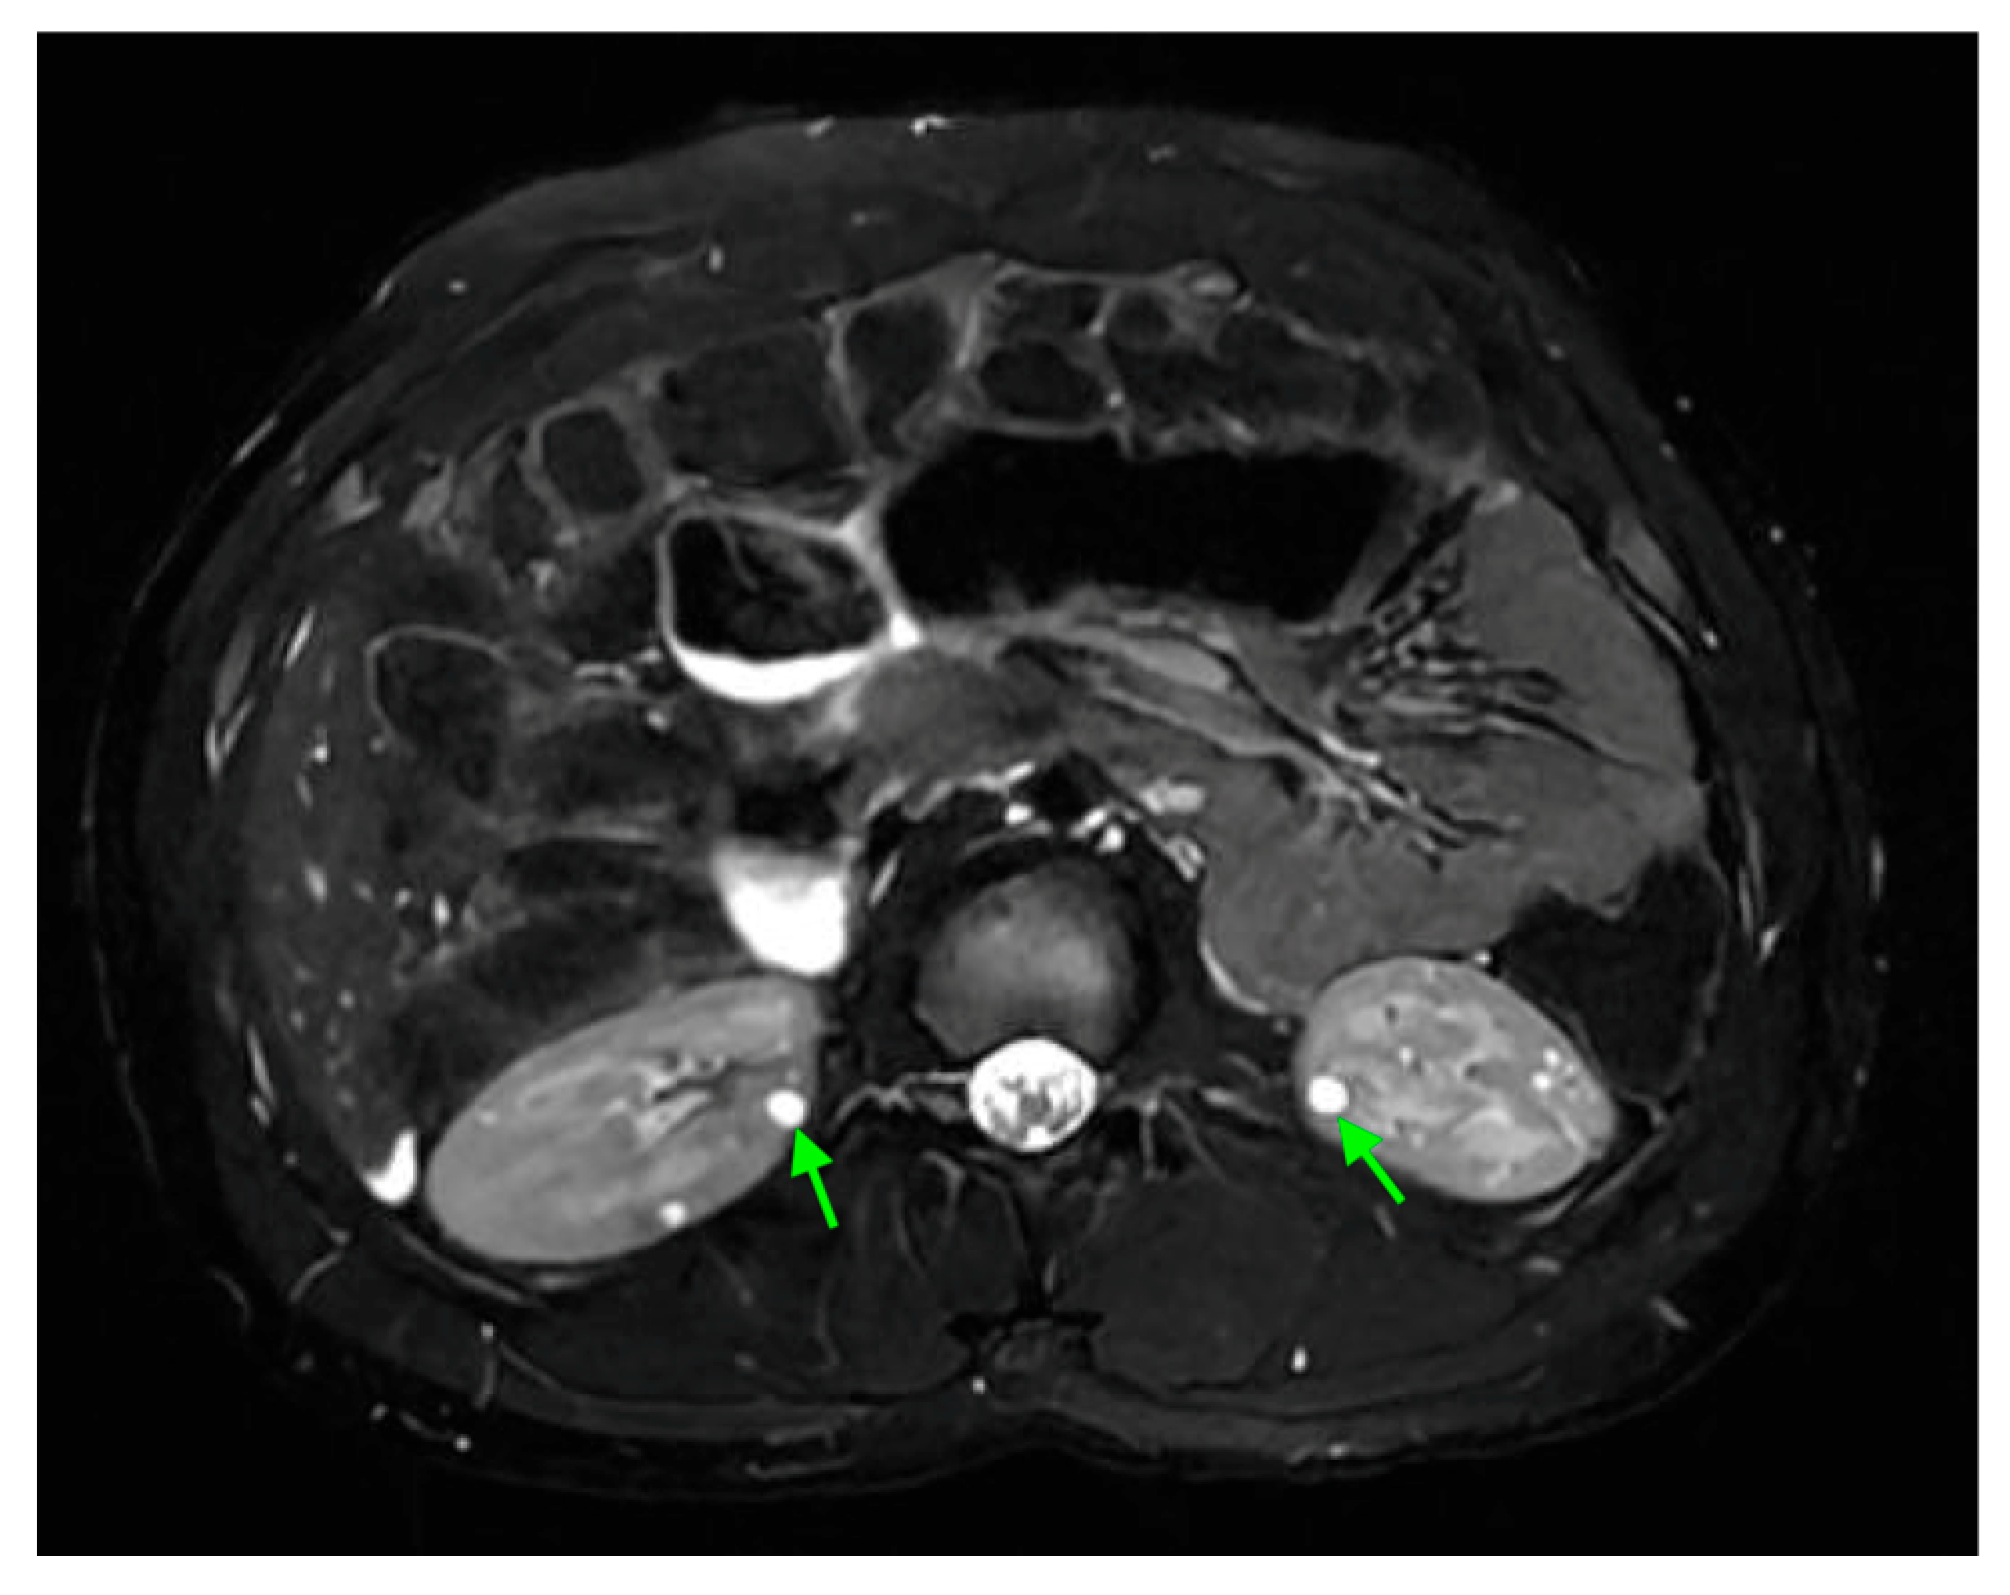

17. Cystic Kidney Disease

18. Tuberous Sclerosis